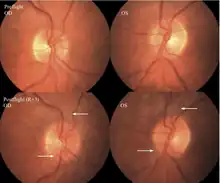

The first U.S. case of visual changes observed on orbit was reported by a long-duration astronaut that noticed a marked decrease in near-visual acuity throughout his mission on board the ISS, but at no time reported headaches, transient visual obscurations, pulsatile tinnitus or diplopia (double vision). His postflight fundus examination (Figure 1) revealed choroidal folds below the optic disc and a single cotton-wool spot in the inferior arcade of the right eye. The acquired choroidal folds gradually improved, but were still present 3 year postflight. The left eye examination was normal. There was no documented evidence of optic-disc edema in either eye. Brain MRI, lumbar puncture, and OCT were not performed preflight or postflight on this astronaut.[5]

Figure 1:Fundus examination of the first case of visual changes from long-duration spaceflight. Fundus examination revealed choroidal folds inferior to the optic disc and a single cotton-wool spot in the inferior arcade of the right eye (white arrow).

The second case of visual changes during long-duration spaceflight on board the ISS was reported approximately 3 months after launch when the astronaut noticed that he could now only see Earth clearly while looking through his reading glasses. The change continued for the remainder of the mission without noticeable improvement or progression. He did not complain of transient visual obscurations, headaches, diplopia, pulsatile tinnitus or visual changes during eye movement. In the months since landing, he has noticed a gradual, but incomplete, improvement in vision.[5]

Figure 2: Fundus examination of second case of visual changes from long-duration spaceflight. Fundoscopic images showing choroidal folds (white arrows) in the papillomacular bundle area in the right eye and left eye and a cotton-wool spot (bottom arrow) at the inferior arcade in the left eye. Both optic discs show grade 1 disc edema.

The sixth case of visual changes of an ISS astronaut was reported after return to Earth from a 6-month mission. When he noticed that his far vision was clearer through his reading glasses. A fundus examination performed 3 weeks postflight documented a grade 1 nasal optic-disc edema in the right eye only. There was no evidence of disc edema in the left eye or choroidal folds in either eye (Figure 13). MRI of the brain and eyes days postflight revealed bilateral flattening of the posterior globe, right greater than left, and a mildly distended right optic nerve sheath. There was also evidence of optic-disc edema in the right eye. A fundus examination postflight revealed a "new onset" cotton-wool spot in the left eye. This was not observed in the fundus photographs taken 3 weeks postflight.[5]

Figure 13: Fundus examination of the sixth case of visual changes from long-duration spaceflight. Preflight images of normal optic disc. Postflight right and left optic disc showing grade 1 (superior and nasal) edema at the right optic disc.

The seventh case of visual changes associated with spaceflight is significant in that it was eventually treated postflight. Approximately 2 months into the ISS mission, the astronaut reported a progressive decrease in his near and far acuity in both eyes. The ISS cabin pressure, CO2 and O2 levels were reported to be within normal operating limits and the astronaut was not exposed to any toxic substances. He never experienced losses in subjective best-corrected acuity, color vision or stereopsis. A fundus examination revealed a grade 1 bilateral optic-disc edema and choroidal folds (Figure 15).[5]

Figure 15: Preflight images of the right and left optic discs (upper). Postflight images of the ONH showing in more detail the extent of the edematous optic-disc margins and glutting of the superior and inferior nerve fiber layer axons OD and OS (arrows) (lower).